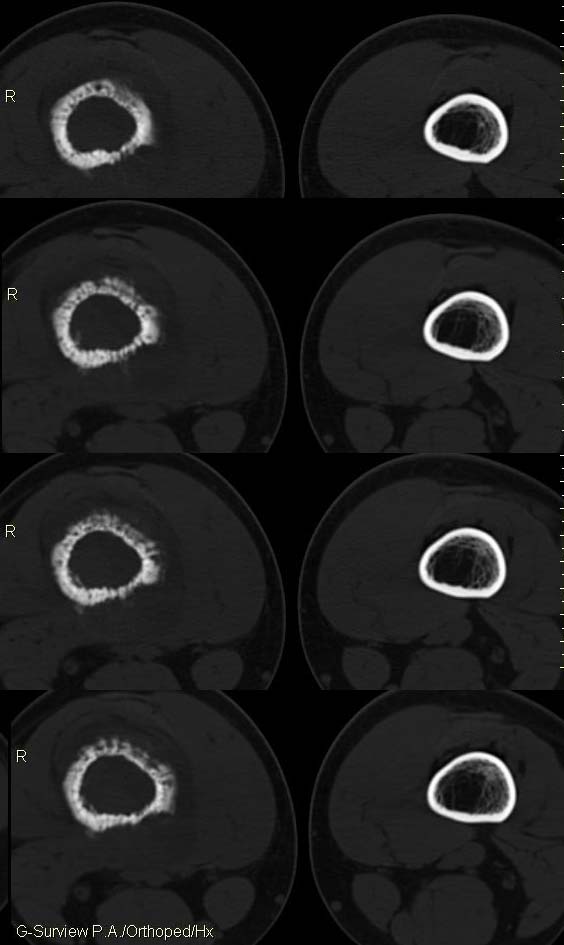

20岁,男,右股骨下端疼痛一个月,无发热,白细胞正常,皮肤不红,肿胀,触痛。

骨膜针状反应,是尤文氏骨肉瘤的典型表现!

右股骨下端很长范围内的髓腔扩大,骨小梁破坏消失,皮质亦呈融骨性破坏,周围脂肪层次紊乱,肌肉受累及密度减低。考虑为:恶性骨肿瘤。请专家们分析骨肉瘤及尤文氏肉瘤的ct征象。

6.ct及mri:能较好地判断肿瘤的范围及侵犯软组织的情况。mri可见瘤体处广泛性骨质破坏,呈软组织肿块影;在t1加权像上呈均匀的长t1信号;在t2加权像上呈很长t2高信号。在ct上显示为源于骨组织的软组织肿块,骨质广泛破坏。

此病例基本可定是恶性骨肿瘤:髓腔内长范围肿块、皮质不规则破坏、软块及软组织浸润、瘤骨及不规则骨膜反应等。可以肯定地除外炎性病变和骨纤。

结合临床还是将尤文氏肉瘤放在前面,骨肉瘤不排除。纤维肉瘤及恶纤组多见老年人,不放在首要诊断范围内。